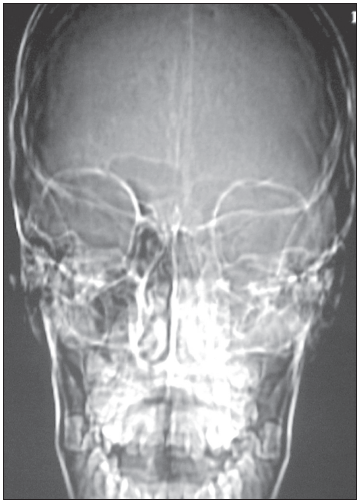

Intraorbital abscess: The radiographs demonstrate opacity of the ethmoid air cells on the left (A and B, blackarrows) with increased opacity of the left maxillary antrum, which is best seen on the frontal view (A, red arrow). The sphenoid and frontal sinuses are unremarkable. The increased density seen on the films results from the filling of the normally aerated sinuses with opaque material (in this case, mucus).

Close inspection also reveals increased density of the left orbit (A, yellow arrow). This density is attributable to edema.